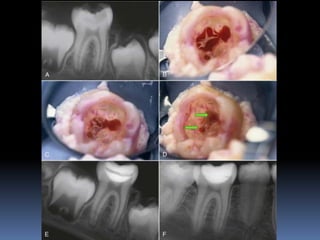

PULPOTOMY

The pulpotomy procedure involves removing only part of the

pulp, eliminating tissue that has inflammatory or degenerative

changes and leaving intact the underlying healthy pulp tissue

The surgical amputation of the coronal portion of an exposed

pulp to protect and preserve the remaining radicular pulp’s

vitality and function

Steps:

 All the carious dentin and pulp to the level of radicular

pulp are removed

- level of CEJ in anteriors

- level of canal orifices in posteriors

 Bleeding from the pulp stump is controlled with moist

cotton pellets and gentle pressure

 The chamber is rinsed with Sodium hypochloride

 The severed pulp is capped with

-

Calcium hydroxide

MTA

 This is then covered with Glass ionomer and the tooth is

restored with a restoration that seals completely

CVEK PULPOTOMY / PARTIAL PULPOTOMY:

The surgical removal of a small portion of the coronal portion

of a vital pulp as a means of preserving the remaining coronal

and radicular pulp.

Technique:

1. Anesthesia and rubber dam isolation

2. The inflamed pulp tissue is removed using a sharp round

bur in a high speed hand piece with water coolant for

superficial 2-3mm of pulp amputaion [Cvek pulpotomy]

3. Or removal of the entire pulp to the level of the canal

orifices using a large Spoon excavator

4. Hemorrhage is controlled by pressure on a cotton pellet

moistened with saline.

[ failure to achieve hemorrhage indicates pulpal inflammation]

The exposed pulp is rinsed with 2.5% sodium hypochlorite

or

hard set calcium hydroxide is placed over the

amputated pulp.

MTA is prepared by mixing MTA powder with saline in the

ratio of 3:1 on a glass slab. The mixture is placed on

the exposed pulp and patted with a moist cotton

pellet.

MTA sets in the presence of moisture. Wet cotton

pellet is placed over MTA and the tooth is restored.